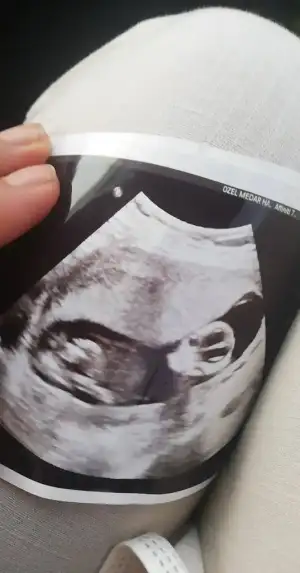

Canım bizede 12+5 de tahminde bulunurmusun karından usd dr bir tahminde bulundu ama net değil dedi🤗

• image.webp

image.webp

16 KB · Görüntüleme: 63

Merhaba yukarıda sanırım arada gözden kaçtı tica etsem banada yorum yaparmısınız 12+5 karından usg🤗

Eklentiler